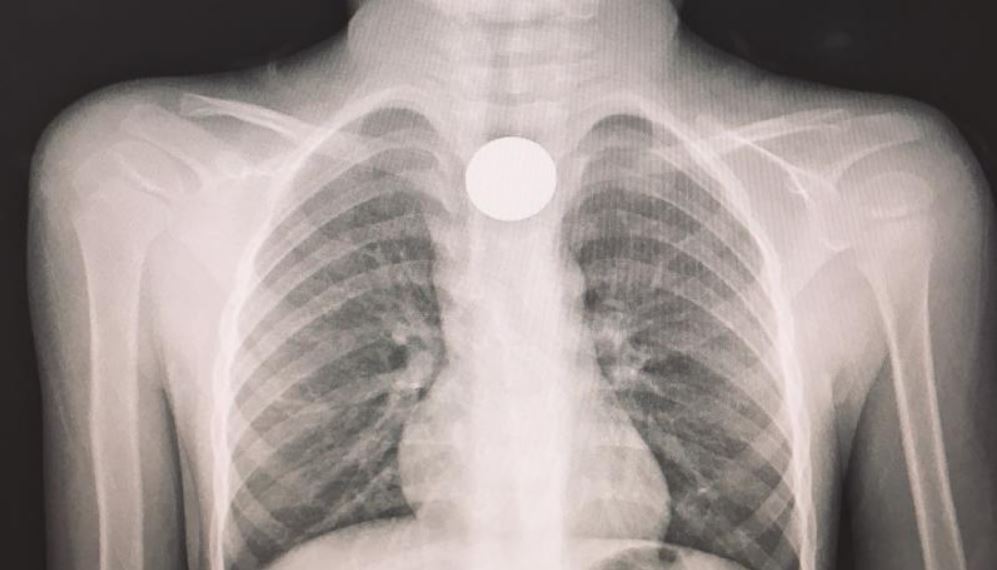

Giunto al pronto soccorso dopo aver ingoiato una moneta, viene trasferito in elicottero all’ospedale di Cosenza dove, dopo un tempestivo intervento, è stato dichiarato fuori pericolo.

“Si è conclusa positivamente la disavventura del piccolo A. M., 4 anni, italiano con genitori stranieri, che in mattinata era stato accompagnato al pronto soccorso dello Jazzolino. A dire dei familiari, il bimbo mentre giocava aveva probabilmente ingerito un corpo estraneo, poiché improvvisamente aveva smesso di parlare e si portava angosciosamente le mani alla gola.”